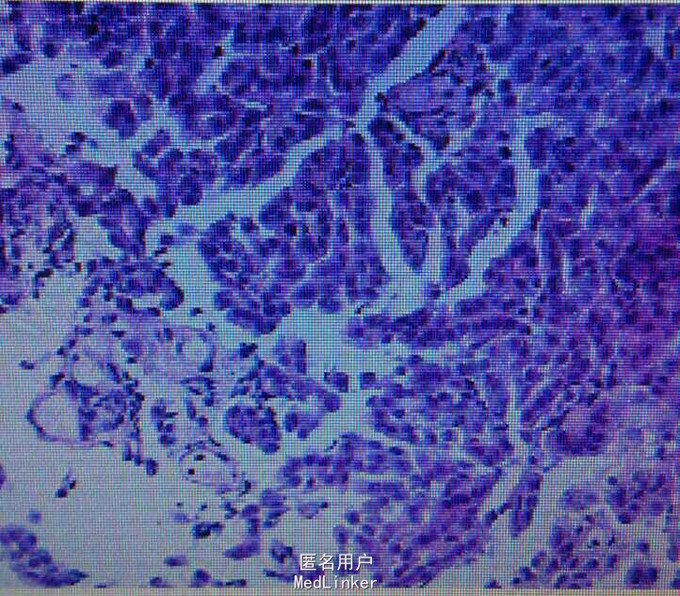

查体右下肺呼吸音减弱,无干湿罗音。心音正常。胸片示右胸膜增厚,少量积液。行胸膜活检示胸膜恶性间皮瘤。

诊断胸膜恶性间皮瘤。治疗力比泰+顺铂化疗,症状好转,胸水吸收。